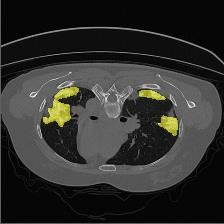

Medical image segmentation is one of the most fundamental tasks concerning medical information analysis. Various solutions have been proposed so far, including many deep learning-based techniques, such as U-Net, FC-DenseNet, etc. However, high-precision medical image segmentation remains a highly challenging task due to the existence of inherent magnification and distortion in medical images as well as the presence of lesions with similar density to normal tissues. In this paper, we propose TFCNs (Transformers for Fully Convolutional denseNets) to tackle the problem by introducing ResLinear-Transformer (RL-Transformer) and Convolutional Linear Attention Block (CLAB) to FC-DenseNet. TFCNs is not only able to utilize more latent information from the CT images for feature extraction, but also can capture and disseminate semantic features and filter non-semantic features more effectively through the CLAB module. Our experimental results show that TFCNs can achieve state-of-the-art performance with dice scores of 83.72\% on the Synapse dataset. In addition, we evaluate the robustness of TFCNs for lesion area effects on the COVID-19 public datasets. The Python code will be made publicly available on https://github.com/HUANGLIZI/TFCNs.

翻译:医学图像分解是医学信息分析的最根本任务之一,到目前为止已经提出了各种解决办法,包括许多深层次的学习技术,如U-Net、FC-DenseNet等。 然而,高精度医学图像分解由于医疗图像中存在固有的放大和扭曲,以及存在与正常组织密度相似的损伤,因此仍是一项极具挑战性的任务。在本文件中,我们建议TFCN(全面革命稠密网络的传输者)通过向FC-DenseNet引进ResLear-Transerferent(R-Transerfor)和Culvacial线性关注区(CLAB)来解决这一问题。TFCN不仅能够利用CT图像中更多的潜在信息来提取特征,而且还能够通过CLAB模块更有效地捕捉和传播语性特征和过滤非神经性特征。我们的实验结果表明,TFCN可以在Syapseion/SymblyDDS上以83CN-72 ⁇ 的分数实现状态。此外,我们在Synapse-DRIS数据设置上,我们还将评估CUTFTFI/LIS的可靠度。